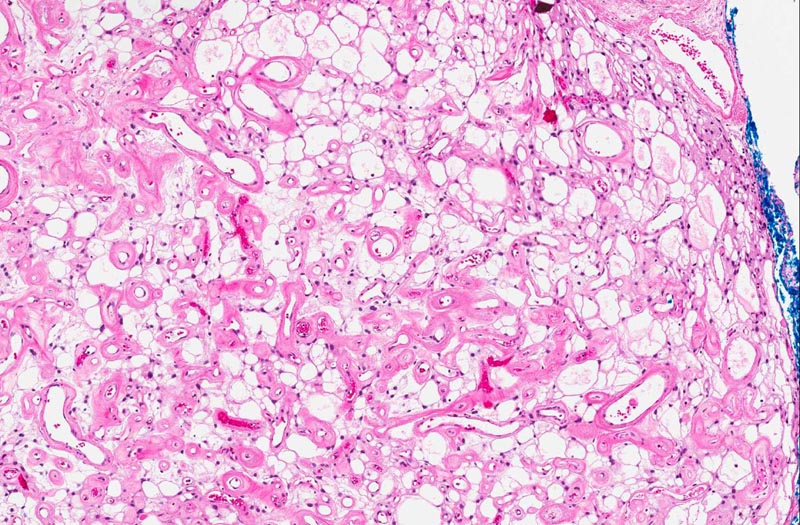

Slide #2 represent the tissue that are

submitted subsequently. The histopathology between this sample and

slide #1 is essentially similar but the there are a lot more highly

sclerotic blood vessels. Some calcifications consistent with

psammoma bodies are present (area 3). The sclerotic blood vessels

dominated the picture. In between the sclerotic vessels are

triangular to irregular nest of stromal cells (area 3). Microcyst

formation is rather common (area 4 and 5).